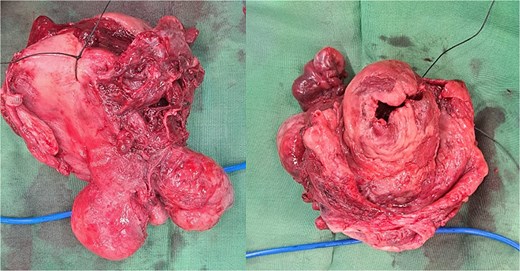

Within the operation, a urinary catheter was inserted and the bladder location was identified. We pushed the mass cranially to reposition the uterus. During repositioning, the cyst mass was ruptured and released serous fluid, exposing the uterine cavity. Another team had started to do a laparotomy and performed a median incision. Intraabdominally, we found a vortex-like structure that had sucked the uterus outside, with a twisted round ligament. We decided to incise the cystic mass to decrease the uterus size, and a sondage was then inserted into the cavity to the cervix inside the abdomen. Then, we made a large bundle of gauze in the sondage handle. We decided to do a double approach to reposition the uterus. The sondage was pulled abdominally and pushed vaginally. Soon, the uterus was reversed, and hysterectomy was performed (Figs 2 and 3). The operation was without complication, with 300 cc of bleeding. Postoperatively, the patient had a good recovery. However, a week after discharge, the wound was not healing properly, with some serous fluid coming out of the wound. A superficial surgical site infection was suspected and managed accordingly, with joint care with internal medicine for her diabetes. The histopathological result was angiomatous leiomyoma submucosum, and no further evaluation was needed.

Submucous leiomyoma that was extracted from the uterus. It showed a cystic white degeneration with serous fluid inside.

The uterus with the cervix. The corpus was already dissected and excised from the submucous leiomyoma.